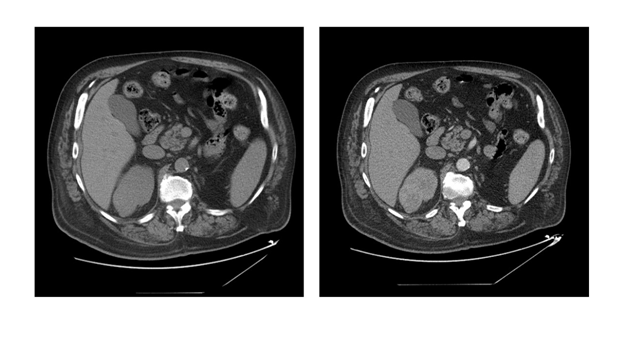

Figure 1 Ct-Scan abdomen/pelvis, with/without IV contrast, 3 phases.

Right: Non-contrast phase.

Left: Arterial phase, right upper pole, enhancing, posterior, close to collecting system, renal mass, 5.2 cm.